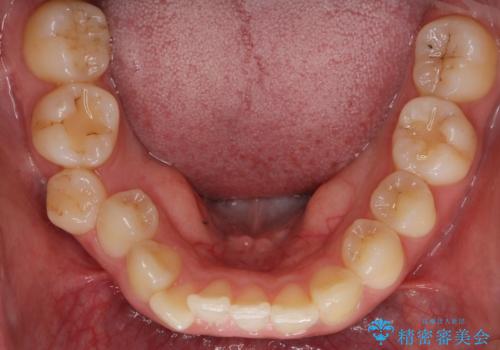

また、右下の奥歯に一部目立たないように部分的なワイヤー矯正を行い、右下の奥歯が反対咬合になっていたのもしっかり中に入れて治療しています。

奥歯の反対咬合を治すのはインビザラインではかなり難しいのですが、しっかり治療できました。